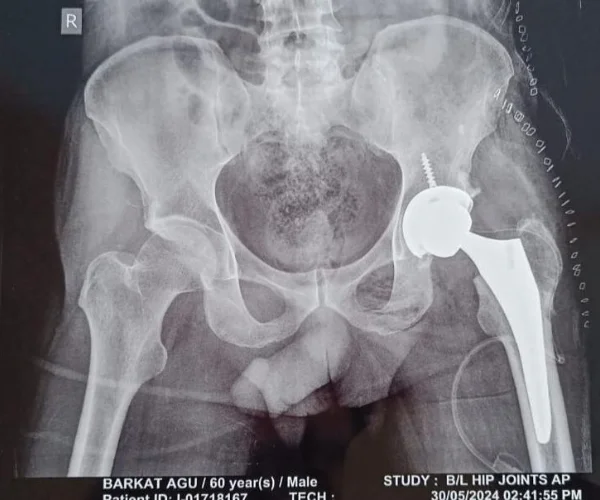

Hip replacement surgery, also known as total hip arthroplasty, is a procedure in which a damaged or deteriorated hip joint is replaced with a prosthetic implant. It is most commonly recommended for patients suffering from:

1. Comprehensive Consultation & Diagnosis Dr. Solunke begins with a thorough evaluation — reviewing your medical history, X-rays, and MRI reports — to determine whether hip replacement is the right course of action for you.

2. Pre-Surgery Planning Using advanced implant selection and templating, Dr. Solunke customises the surgical plan to your anatomy, age, activity level, and long-term goals.